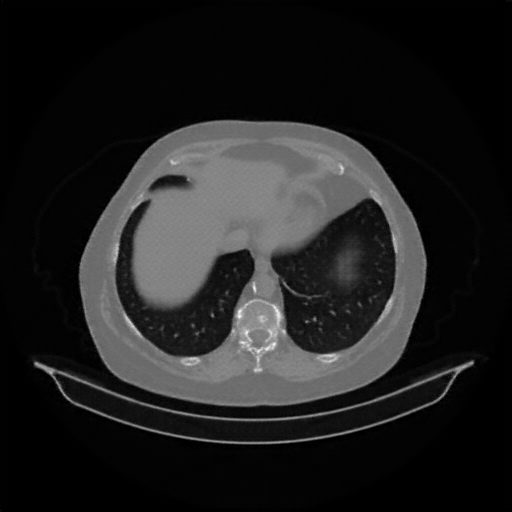

Original VENOUS CT scan

Lung window (WL -600, WW 1500 β†’ Low βˆ’1350, High +150)

Actual HU range: [-1024.0, 150.0]